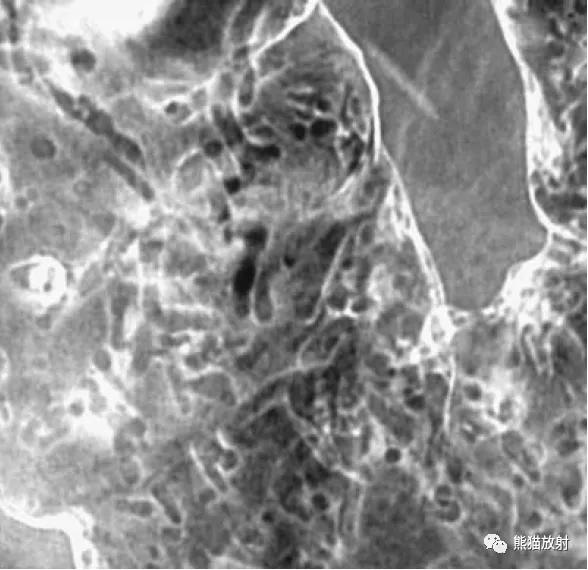

盲肠白塞病(Behcet syndrome)。可见散发的小溃疡。

克罗恩病(Crohn's disease)。存在广泛的丝状息肉。